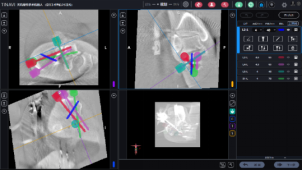

在骨科中心主任吴超的带领下,团队采用了天玑Ⅱ骨科手术机器人为程某开展了微创手术治疗,该手术时间短、创伤小、出血少、透视次数少,同时实现了骨折块的解剖复位和精准的螺钉置入及固定;术后影像学显示患者关节面完全复位,螺钉位置良好,固定可靠。